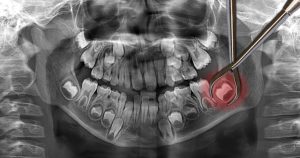

Top 5 Most Common Questions About Wisdom Teeth Answered Wisdom teeth, often referred to as third molars, are a common topic of discussion in dental

Busting the Top 5 Myths About Wisdom Teeth Removal You Need to Know

Top 5 Myths About Wisdom Teeth That Need to Be Busted Wisdom teeth are often a source of confusion and concern for many individuals. As

Mastering Your Prep for Wisdom Teeth Removal Like a Pro

How to Prepare for Wisdom Teeth Removal Like a Pro Wisdom teeth removal is a common dental procedure that many individuals face during their late

Understanding the Connection Between Wisdom Teeth Removal and Your Oral Health

The Connection Between Wisdom Teeth and Oral Health Understanding the relationship between wisdom teeth and oral health is essential for maintaining a healthy smile throughout